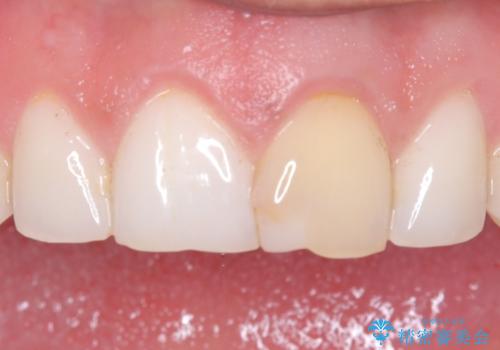

[ セラミック治療 ] 前歯の見た目を改善したい

![[ セラミック治療 ] 前歯の見た目を改善したいの症例 治療前](https://seimitsushinbi.jp/wp/wp-content/uploads/2025/10/IMG_9990-2-500x350.jpg?v=1761816440)

![[ セラミック治療 ] 前歯の見た目を改善したいの症例 治療後](https://seimitsushinbi.jp/wp/wp-content/uploads/2025/10/IMG_9934-500x350.jpg?v=1761816431)